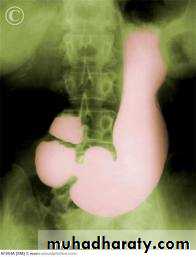

Sliding herniaOn the left initially, GE junction is below the esophageal hiatus. Later, stomach protrudes through hiatus

Para esophageal hernia

On the far left gas filled gastric funds (asterisk) protrudes through hiatus but GE junction (arrow) is below diaphragm